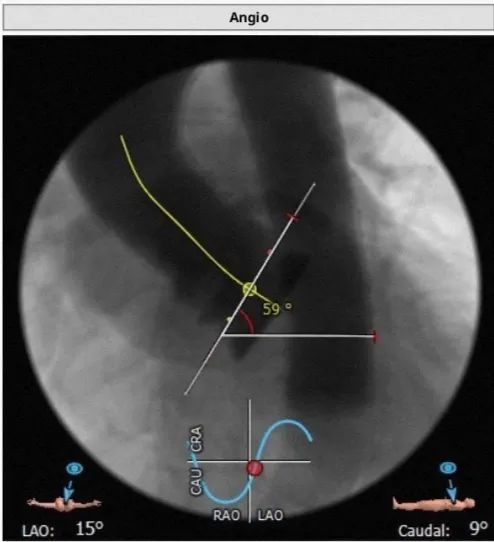

升主动脉直径:31.2,心脏夹角:59度